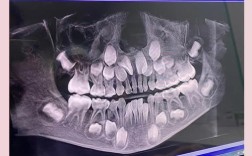

- 机制: 如果正畸治疗前没有进行全面的检查(包括详细的口腔检查、必要的X光片如根尖片、曲面断层片,甚至CBCT评估牙根形态和长度),未能发现潜在的牙髓问题或牙根吸收高风险因素。

- X光片: 显示牙根吸收、根尖周骨质破坏暗影等。